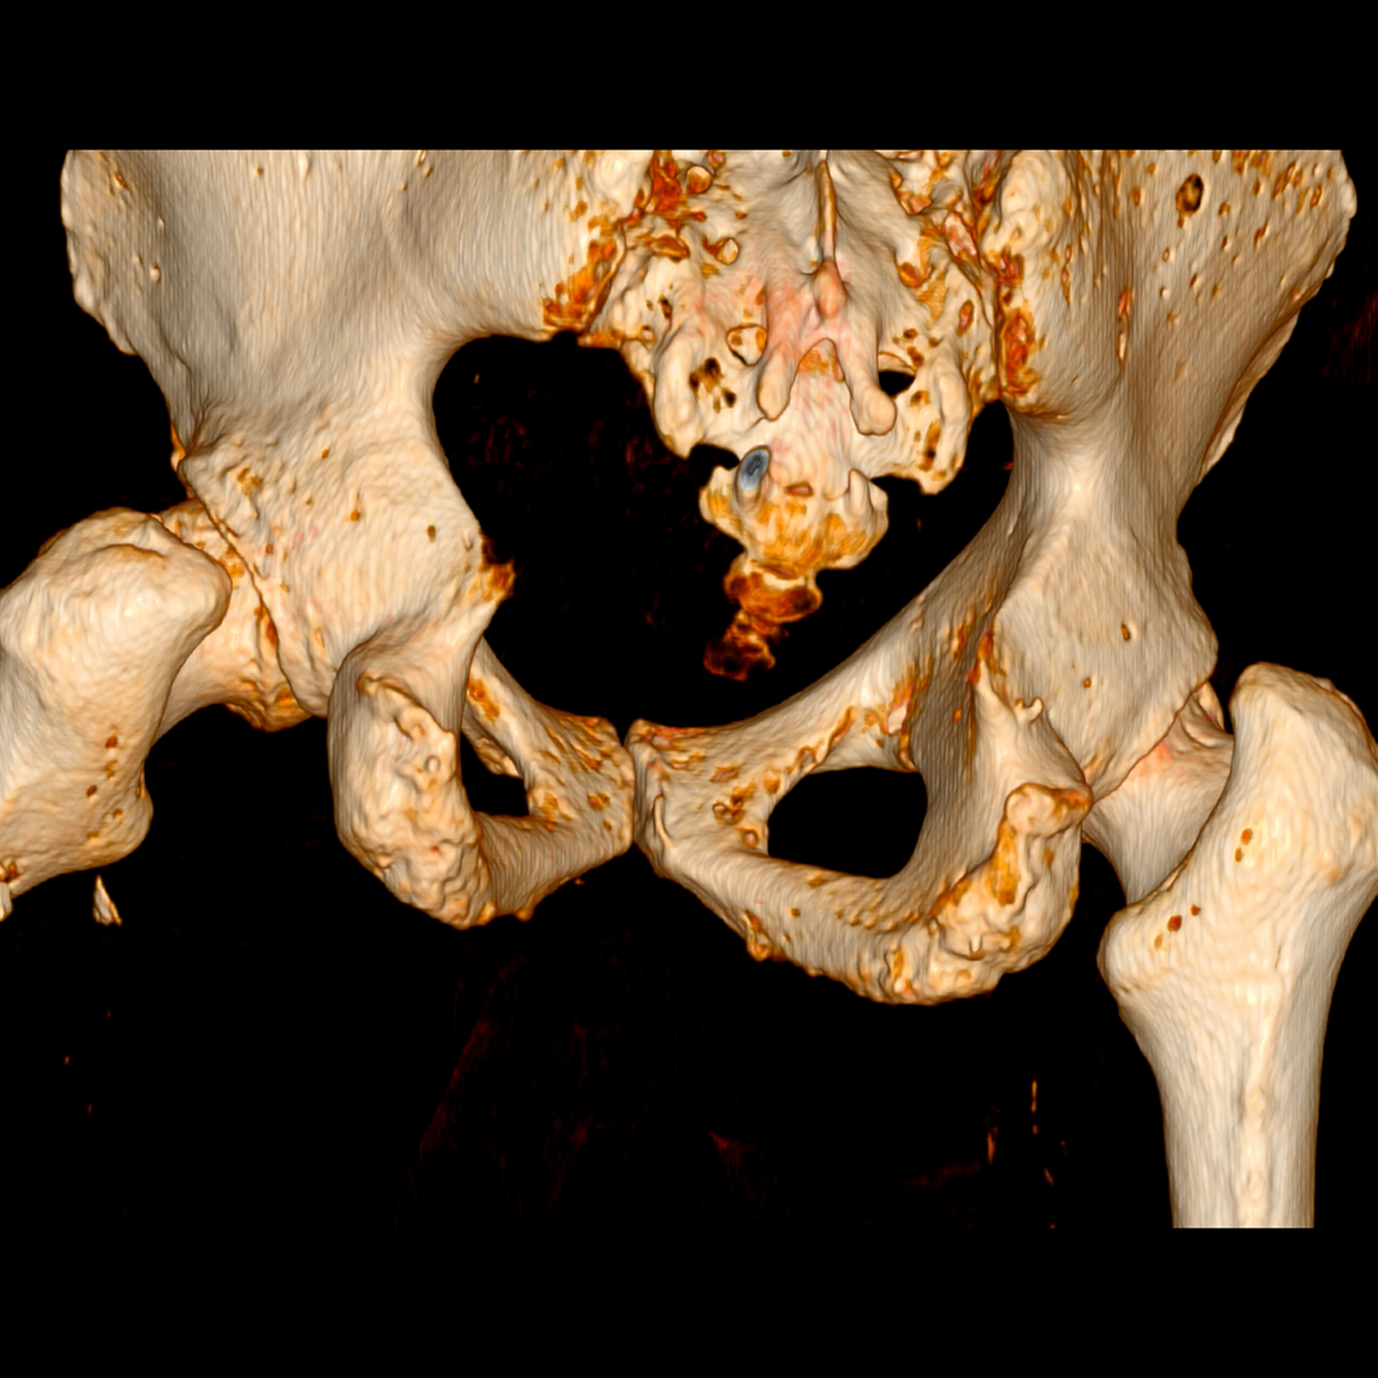

- • TEM de Pelvis y Caderas

CCKlínicalínica G'STAR cuenta con equipos de última generación que permiten cortes finos menores a 1mm, reconstrucción 3D y menor radiación para un diagnóstico preciso.

Ejemplos de estudios realizados en nuestra clínica.